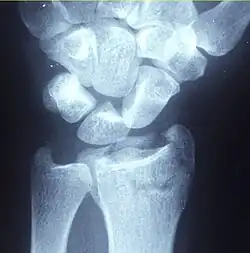

| Other names | Broken wrist[1] |

| A Colles fracture as seen on X-ray: It is a type of distal radius fracture. | |